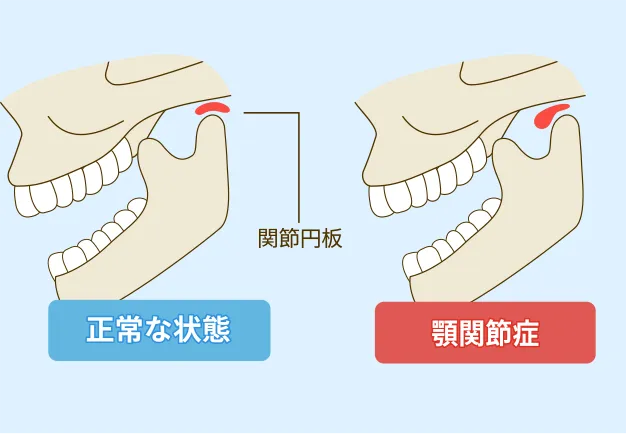

歯だけではなく、顎、骨、筋肉が正しく機能することで健康的に噛むことが可能になります。咬み合わせを修正することは呼吸や全身のバランスの改善にも繋がります。おかしな筋肉の使い方は顎関節症などのトラブルを招くため、骨格から口腔環境を整えます。

顎の関節が正常な位置にある

顎の関節の位置にズレがなく、顎関節と歯のバランスの調和が取れている。